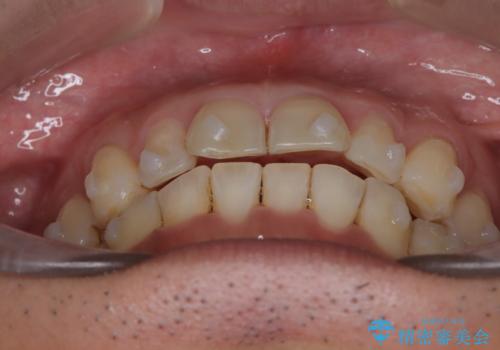

【インザライン】前歯の凸凹を治したい

- 前歯の凸凹を主訴に来院されました。

下顎位が右方に変異しており、外科矯正も提案しましたが患者様は希望されず、インビザラインにて治療を完了しております。

叢生のスペースを確保するために、臼歯部の遠心移動を行っています。

今回の治療計画は上顎の正中を顔と揃えることを優先しています。